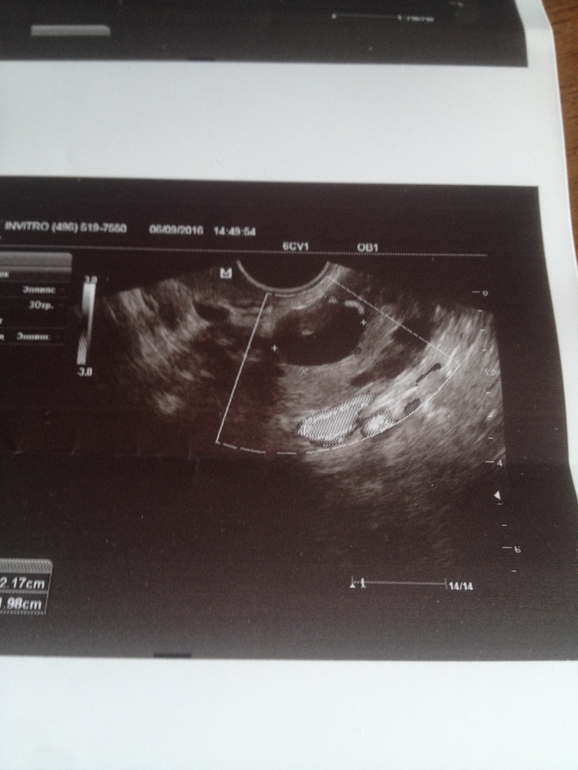

Сегодня на 28 ДЦ пошла на УЗИ (в другое место), т.к. 2 дня очень обильные выделения ЯБ. В результате эндометрий 13мм, в ЛЯ формируется желтое тело 20х22мм, небольшое кол-во жидкости есть. Узистка сказала, что прямо сейчас происходит овуляция, ЖТ только начало формироваться.

Это как понимать? За 4 дня фоллик с 11мм так вырос и совулировал? посмотрите фотки, плиз, кто понимает, я в этом полный профан. И как думаете в постель уже поздно ложиться?

А подскажите кто разбирается ЖТ на каком из этих фото?

на 2 фото больше похож на фолликул, так как края ровные, но внутри серое включение, может формируется жт.